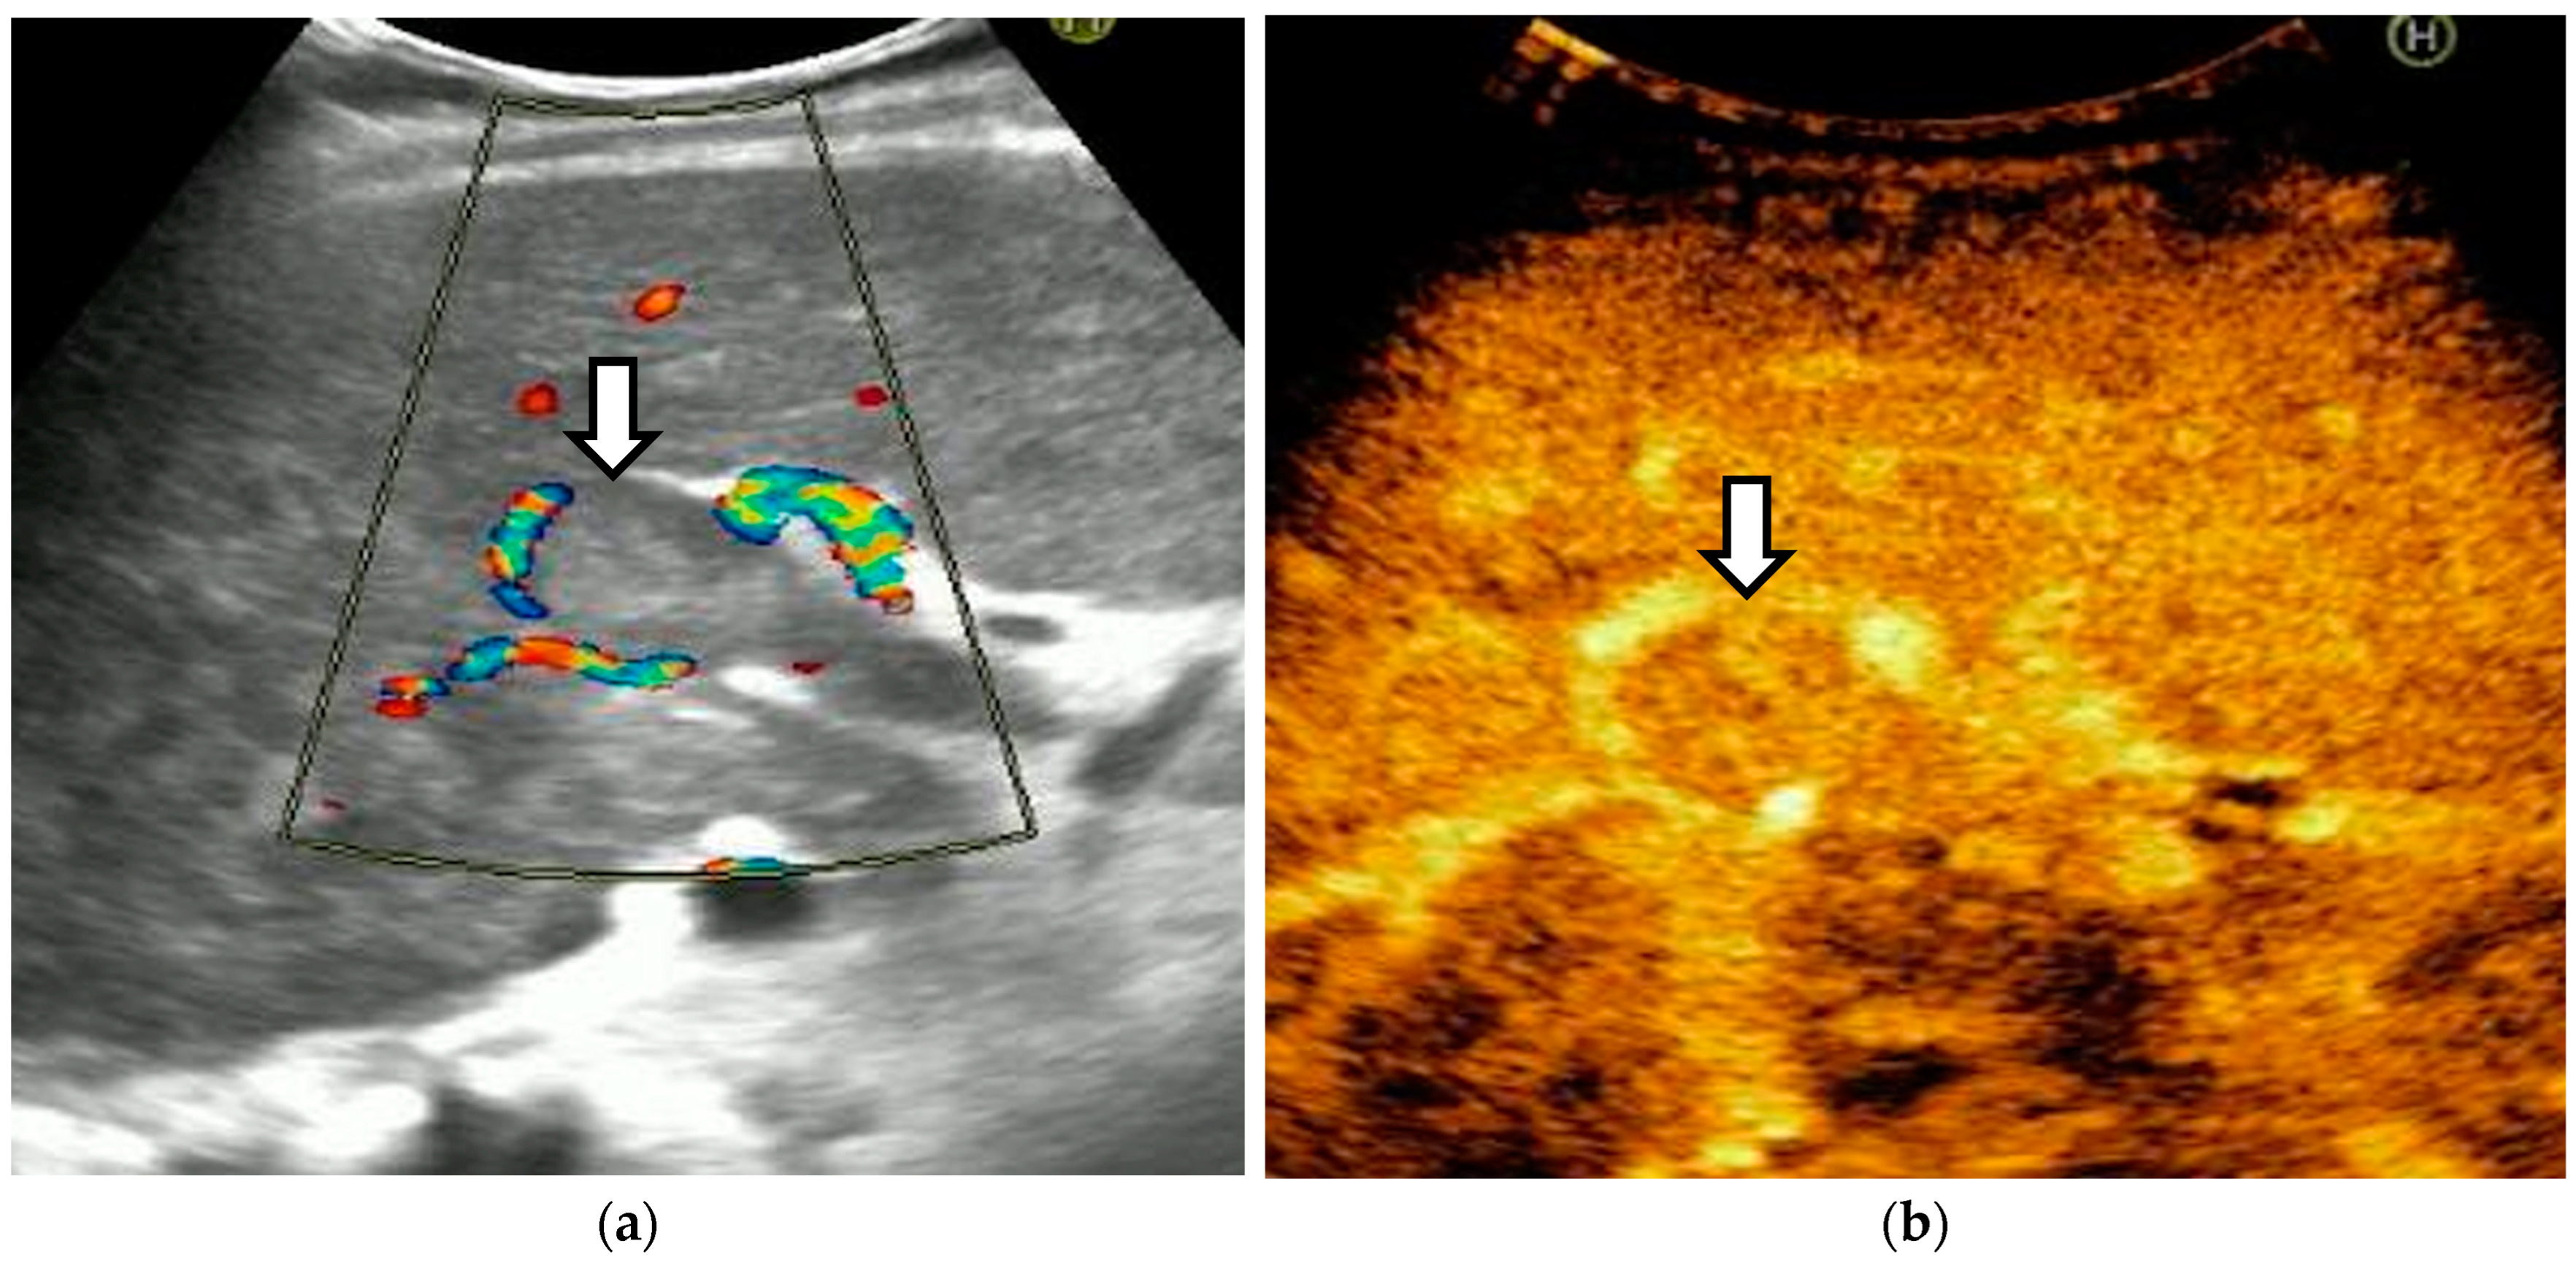

The diagnosis of PVT and PC is made by imaging procedures (transabdominal ultrasound with a Doppler or contrast-enhancing computed tomography scan, magnetic resonance imaging, or angiography in the case of therapeutic intended procedures) [1,3,12,13,14,21,29]. Transabdominal ultrasound is a reliable procedure in 60–100% of cases, with an anechoic aspect in recent cases (requiring Doppler examination or CEUS) and a hypoechoic or hyperechoic aspect in chronic cases [22,29]. Doppler examination may show an anechoic or hypoechoic thrombus and a slower (<15 cm/sec) or absent portal blood flow, and is considered the gold standard (color Doppler) for the diagnosis of PC [1], with a sensitivity and specificity of 95% (Figure 1 and Figure 2) [22]. CEUS can help the diagnosis of benign or malignant PVT, can characterize associated focal liver lesions [30], allows a better characterization of PVT [31], and also permits better detection of PC—Figure 3 and Figure 4 [32]. CT scan and MRI (Figure 5 and Figure 6) are more accurate for the evaluation of liver causes (HCC, abscesses, and other tumors) or other local causes (pancreatitis, diverticulitis, and appendicitis), and for complications (bowel infarction or perforation), and may show permeability of the portal venous system and the flow direction [1,22]. Malignant PVT has intra-thrombus arterial signals on CT, MRI, and/or CEUS, with portal vein diameter frequently 23 mm or above, and with the presence of the tumor at imaging examination (Figure 4 and Figure 6) [21].

Figure 6.

Malignant portal vein thrombosis. (a) In standard ultrasound, the portal vein is large with an occlusive thrombus (arrowhead). (b) CEUS reveals enhancing tissue within the vessel lumen (arrowhead) in the arterial phase.

Transabdominal ultrasound with Doppler protocol (Figure 1a,b and Figure 2a,b), CT scan (Figure 3a,b), and MRI (Figure 4a,b) were used for the diagnosis in 88.9, 75.1, and 15% of cases, respectively. CEUS was used for the diagnosis in 49 cases (25.9%) but in only 29 cases was it used for the evaluation of the thrombus, and in two cases for cavernoma diagnosis (Figure 5a,b and Figure 6a,b).

CEUS detected contrast uptake in none of 10 benign thrombi (100%) and 17 of 19 (89.47%) malignant thrombi. The two unenhanced malignant thrombi were small and incomplete. All the malignant thrombi exhibited early blood flow (arterial phase, up to 30 s after contrast injection). Malignant thrombi had the same enhancement pattern as the tumor from which they originated, including rapid arterial phase hyperenhancement and slow or weak portal venous washout. In 20 cases, we visualized small hyperechoic portal vein lumen, which reflects an old thrombosis with or without PC.